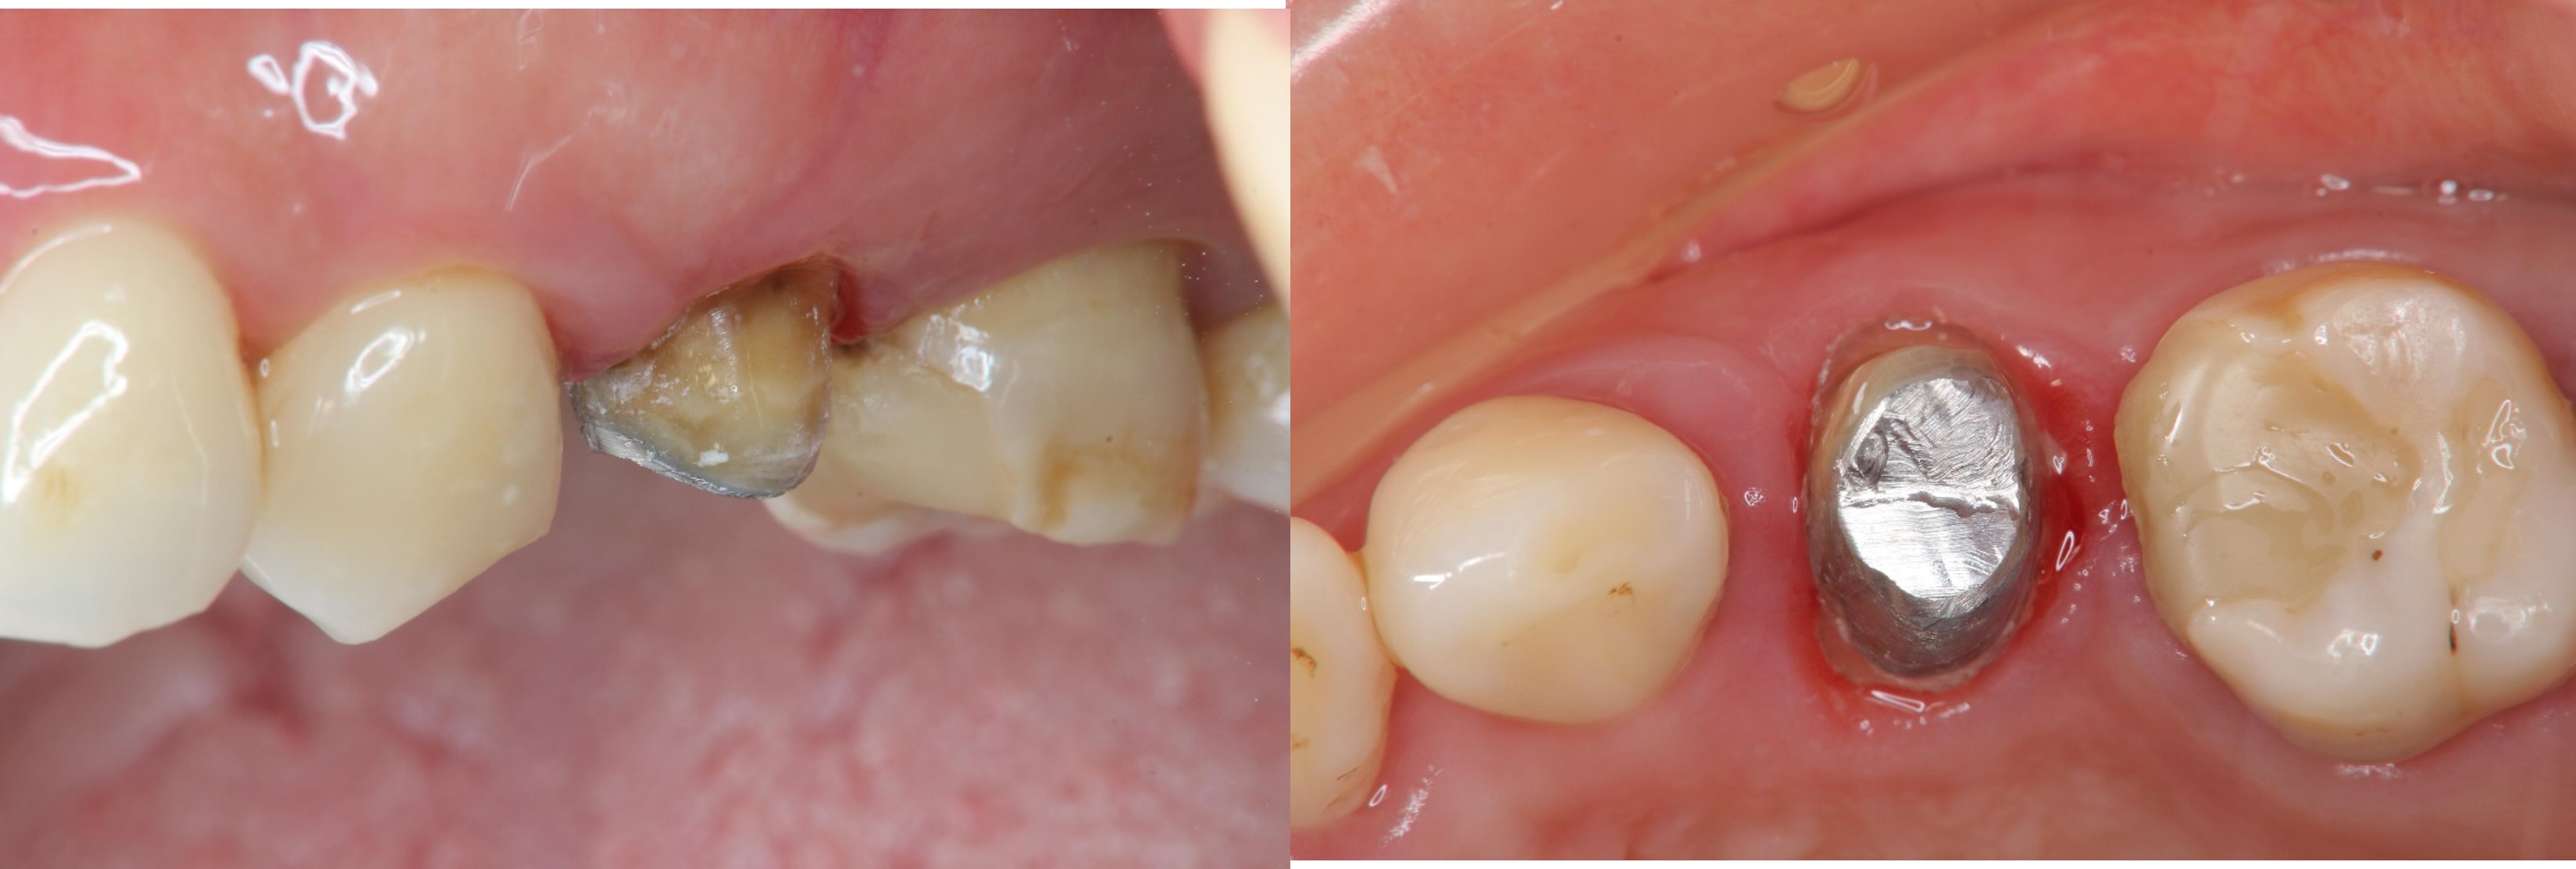

治療前,右上第二小臼齒疼痛

水雷射牙冠增長手術

鑄造金屬釘柱

膺復前評估牙齦、牙齒狀態